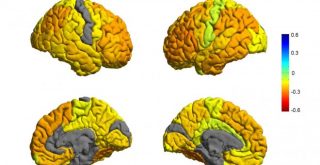

Hallada una causa del trastorno bipolar

Una investigación revela el mal funcionamiento de una proteína en el cerebro en los pacientes de trastorno bipolar que responden al litio

Una investigación revela el mal funcionamiento de una proteína en el cerebro en los pacientes de trastorno bipolar que responden al litio

El diagnóstico del trastorno bipolar es sin embargo complicado de establecer, y es que se sabe muy poco acerca del desorden bipolar a nivel molecular. En este contexto, las investigaciones realizadas recientemente para determinar por qué el litio funciona para muchos pacientes acerca a los científicos a un mejor entendimiento del trastorno bipolar y su génesis.

El diagnóstico del trastorno bipolar es sin embargo complicado de establecer, y es que se sabe muy poco acerca del desorden bipolar a nivel molecular. En este contexto, las investigaciones realizadas recientemente para determinar por qué el litio funciona para muchos pacientes acerca a los científicos a un mejor entendimiento del trastorno bipolar y su génesis.

El estudio fue desarrollado por la Facultad de Medicina Keck de la Universidad del Sur de California, y está publicado en Molecular Psychiatry.